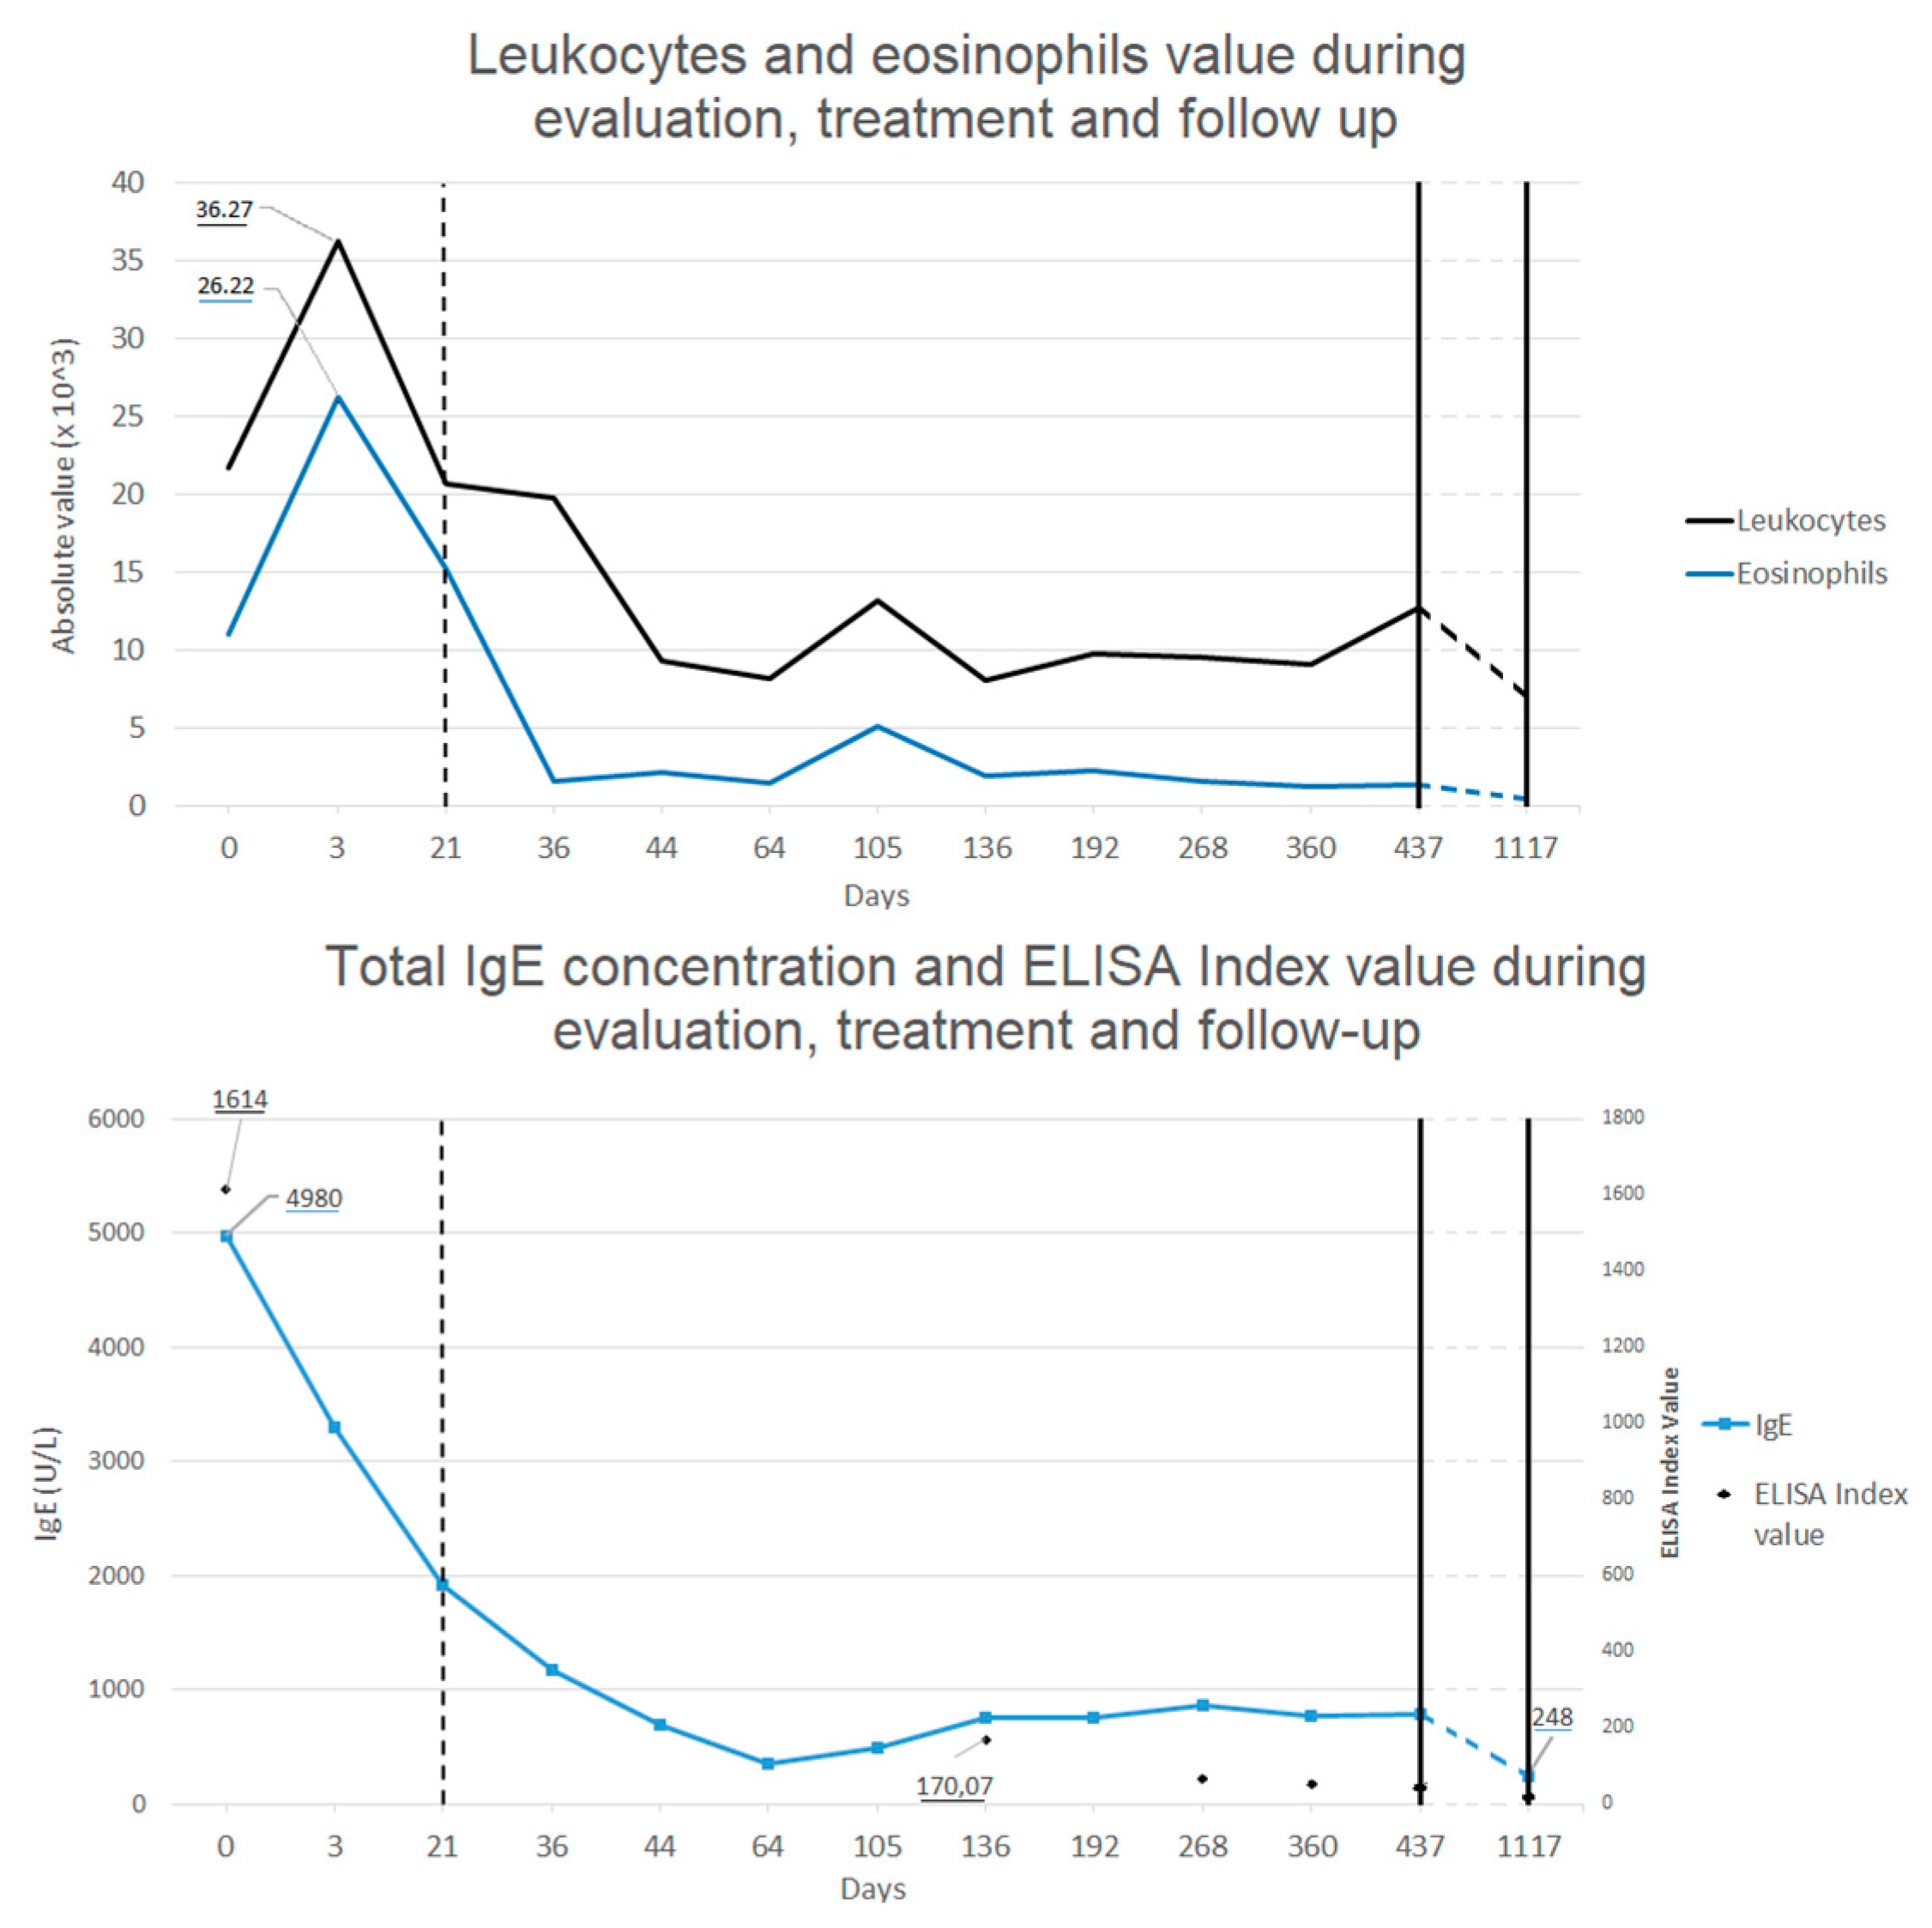

Once diagnostic evaluation was concluded, treatment with albendazole (15 mg/kg/die orally twice a day, for 5 days) and prednisone (0.8 mg/kg/die for 5 days orally to prevent allergic reaction to parasitic massive lysis) was started. Treatment was well tolerated by the patient without any side effect, with a rapid improvement of the symptoms (disappearance of the fever and appetite recovery) and of the laboratory findings (eosinophilia and IgE reduction, decrease of RCP and ESR). An abdominal echography was repeated after 4 days of therapy, showing significant reduction of the hepatic lesions.

Follow-up was made by repeating blood tests all over 2 years after treatment, showing progressive decrease in eosinophilia and total IgE concentration back to normal value (see

Figure 3), and with echografic controls. Almost normal levels of eosinophils and total IgE were reached after a rapid decrease two weeks after the treatment. ELISA test for

Toxocara continued to show positive results even after 1 year after the treatment, even if blood level of eosinophils and total IgE levels were back to normal values and IL-5 concentration was in range. After 1 month from treatment, abdominal echography was not able to find most of the hepatic lesions previously described, whereas after 1 year only some calcific hepatic lesions were visible (in the same area where the biggest ones where described). A thoracic and abdominal CT done after one year confirmed these finding and showed the disappearance of the pulmonary lesions (see

At a final control made after 2 years, no sign of infection was found at the blood tests (normal value of eosinophils, ERS, RCP and total IgE levels) and the abdominal echography showed no modifications from the one performed the previous year. ELISA test for Toxocara was still positive. An ophthalmologic examination confirmed the absence of local infection. The father reported good conditions of the boy all over the period after the treatment, with no symptoms or signs linkable to the previous Toxocara infection.